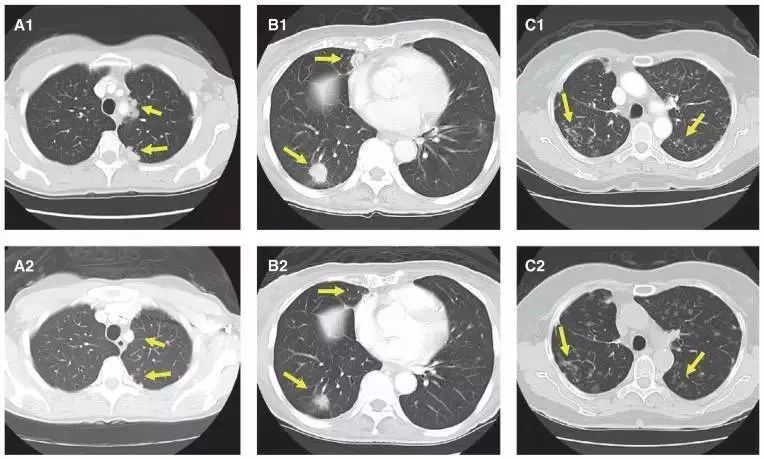

上图中展示了3位RET融合的肺癌患者使用卡博替尼治疗的疗效展示。

A1图患者发现TRIM33-RET基因融合,卡博替尼治疗4周后左肺叶肿瘤明显缩小(A2)

B1图患者发现KIF5B–RET基因融合,卡博替尼治疗4周后右肺双病灶明显缩小(B2)

C1图患者发现KIF5B–RET融合,卡博替尼治疗4周后病灶稳定。